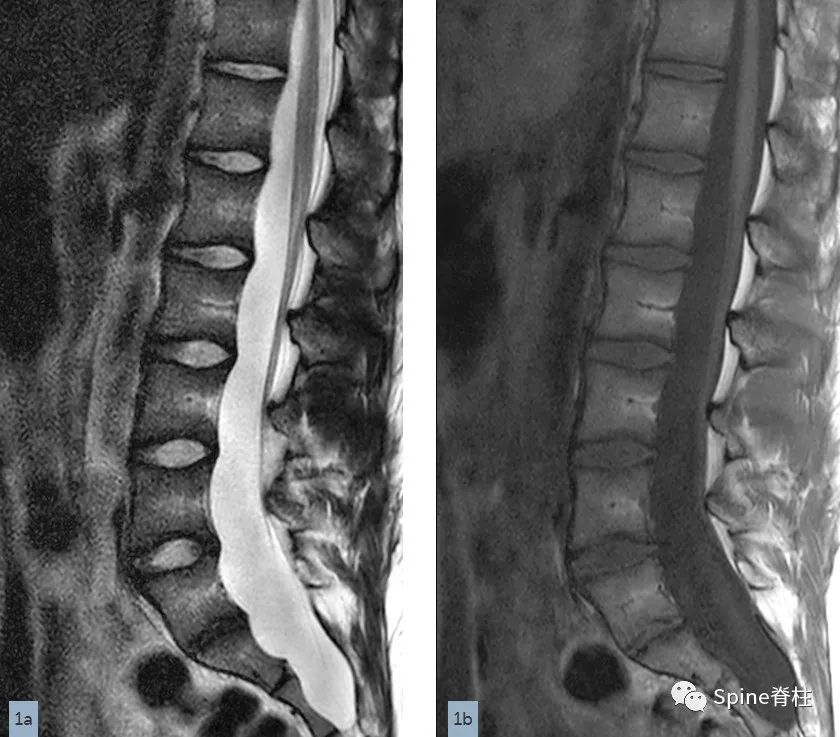

一名18岁男性因腰痛接受MRI检查,下图为矢状位T2(1a)和T1加权像(1b)、S1水平横断面T2(1c)和T1加权像(1d)。

在矢状位T2(2a)和T1加权像(2b)上,多节段椎体后壁呈扇形缺损,缺少硬膜外脂肪(红色箭头),S1处的硬膜囊直径大于L4处。横断面T2(2c)和T1加权像(2d)提示硬膜囊膨胀,S1椎体后壁再次证实硬膜外脂肪缺失(红色箭头)。 其影像学表现符合硬膜扩张的诊断